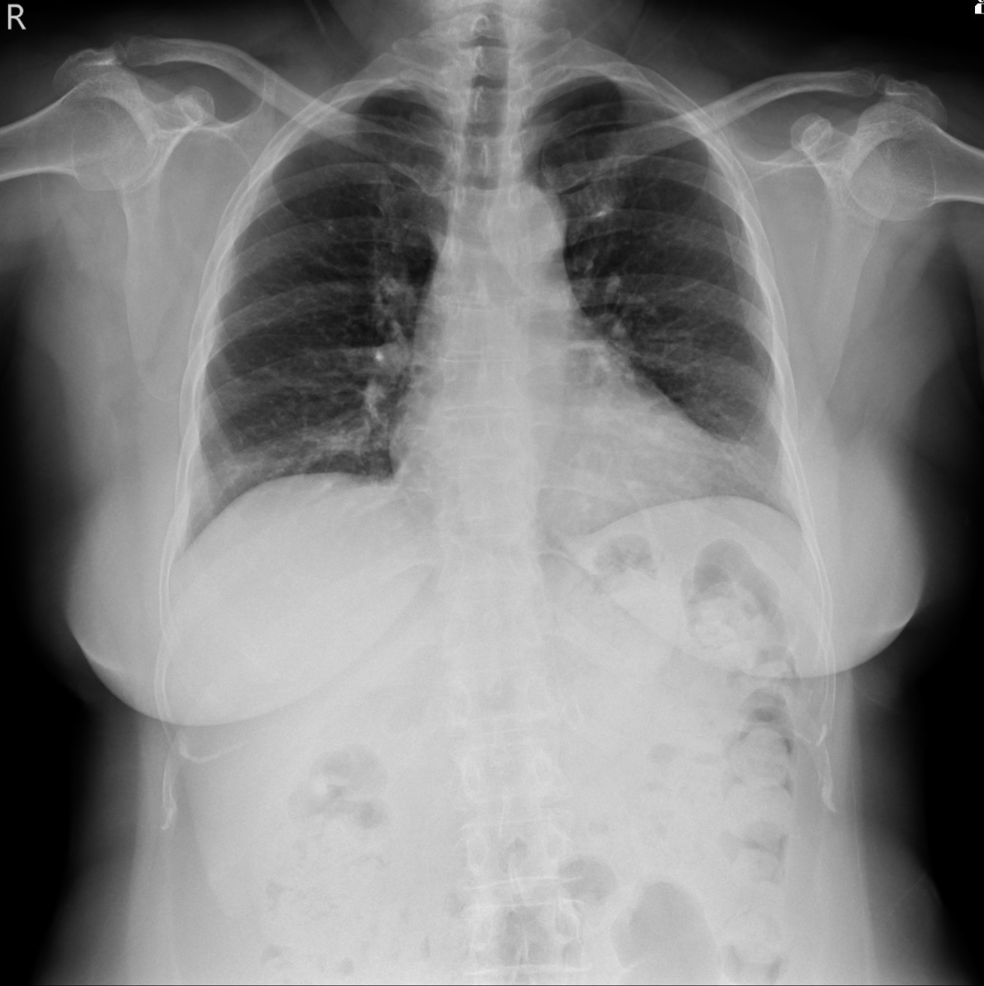

Relevant Test Results Prior to Catheterization

Normal CXR.Normal sinus rhythm, without ST-T changes in EKG